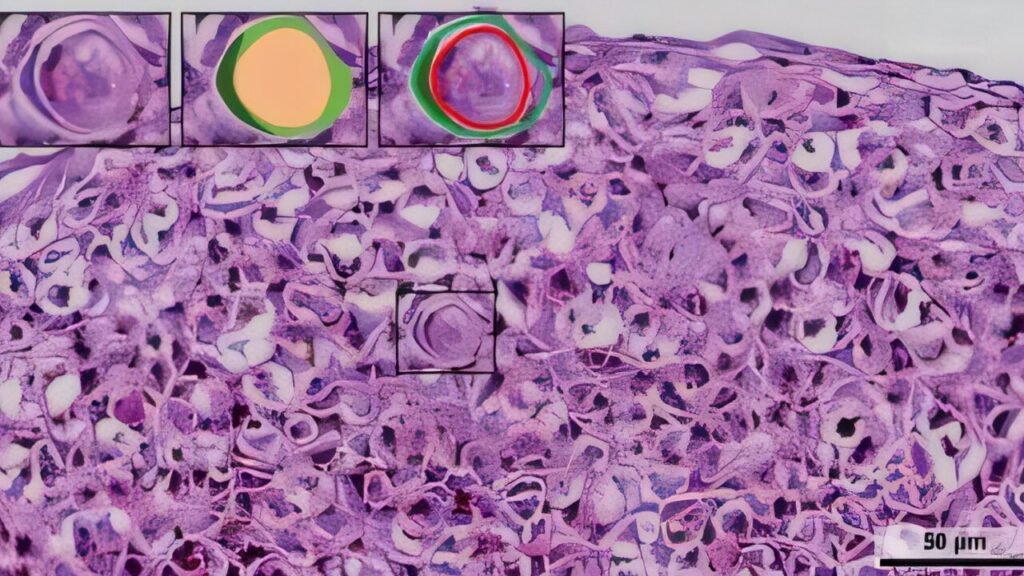

Using a combination of innovative approaches, the team analyzed gene expression patterns in oral cancer cases, recreated tumor environments in laboratory models, and utilized spatial transcriptomics to map gene activity within tissue samples. Their findings revealed that the presence of cancer-associated fibroblasts increased the formation of cell-in-cell structures in tumor spheroids, indicating higher metabolic activity within these structures.

Looking ahead, the researchers hope to integrate cell-in-cell detection into standard cancer diagnostics and explore the potential of AI-based pathology tools that utilize these structures for prognosis and treatment planning. By unraveling the mechanisms of tumor cell cannibalism, this research has the potential to revolutionize cancer treatment strategies and improve outcomes for patients with oral cancer.